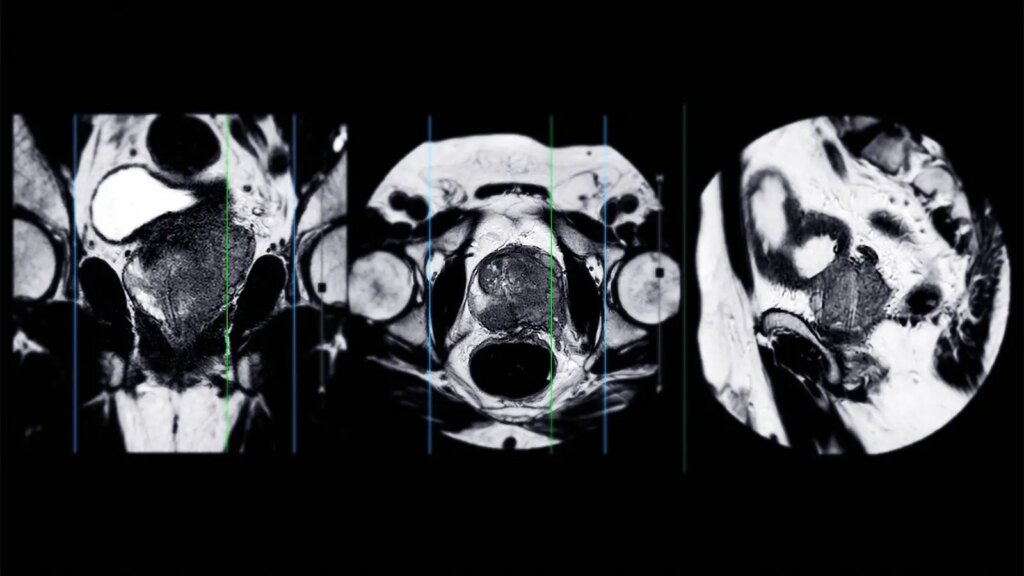

- A pretreatment MRI in men undergoing radical prostatectomy can provide independent prognostic value for oncologic outcomes, a systematic review and meta-analysis indicated.

An MRI before treatment in men undergoing radical prostatectomy can provide independent prognostic value for oncologic outcomes, according to results from a systematic review and meta-analysis.

Across 40 studies, MRI-detected extraprostatic extension was independently associated with biochemical recurrence (pooled HR 2.16, 95% CI 1.84-2.54), metastatic failure (HR 3.18, 95% CI 2.04-4.97), and prostate cancer-specific mortality (HR 10.93, 95% CI 5.05-23.65), reported Georgios Agrotis, MD, PhD, of the Netherlands Cancer Institute in Amsterdam, and colleagues.

MRI-detected seminal vesicle invasion was independently associated with biochemical recurrence (HR 2.74, 95% CI 2.06-3.65) and metastatic failure (HR 5.58, 95% CI 1.15-27.13), they wrote in JAMA Oncology.

In addition, several quantitative MRI-derived parameters were prognostic for biochemical recurrence: Prostate Imaging Reporting and Data System scores of 4 or 5 (HR 2.15, 95% CI 1.82-2.55), tumor diameter ≥20 mm (HR 2.35, 95% CI 1.71-3.24), and apparent diffusion coefficient values less than 0.9 × 10-3 mm2/s (HR 2.39, 95% CI 1.82-3.14).